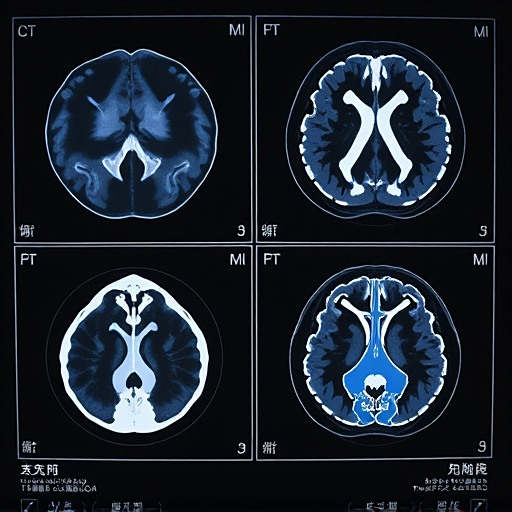

临床诊疗方面,医生可以利用元宇宙技术进行三维可视化诊断。通过整合患者的CT、MRI等影像数据,构建出患者个性化的免疫系统数字孪生模型。医生可以360度全方位观察病灶部位的免疫反应情况,为制定精准治疗方案提供支持。

三维可视化技术让医生能够更直观地观察患者的免疫系统状态。通过构建患者免疫系统的数字孪生模型,医生可以360度全方位查看免疫细胞的活动情况,精确识别病灶位置。这种可视化技术大大提高了诊断的准确性。